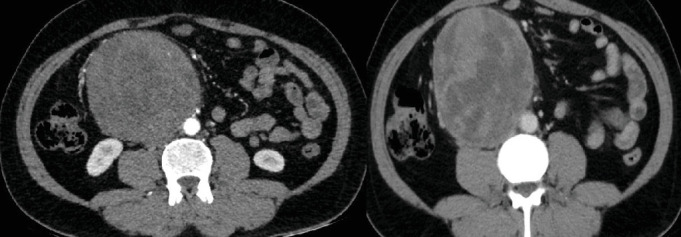

Background: Primary retroperitoneal seminoma is an exceedingly rare type of germ cell tumor, accounting for less than 5% of all such tumors. These tumors are typically large at presentation due to their slow growth and the nonspecific nature of symptoms, which often leads to delayed diagnosis. Case Presentation: A 40-year-old male presented with intermittent abdominal pain and a palpable lump in the right paraumbilical region. Ultrasonography revealed a large retroperitoneal mass. Fine needle aspiration cytology confirmed the diagnosis of poorly differentiated malignant tumor, for which he was evaluated with CT-angiogram of the abdomen and FDG PET-CT scans, which showed a large retroperitoneal mass. The patient, then, had a surgical resection of the mass, with postoperative histopathological and immunohistochemical diagnosis of primary retroperitoneal seminoma, and then underwent three cycles of BEP chemotherapy. Scrotal ultrasonography showed no testicular abnormalities, obviating the need for orchiectomy. FDG PET showed a complete response following treatment completion. Postoperative management included routine monitoring of tumor markers and follow-up imaging, which showed a complete response. Conclusion: This case highlights the diagnostic and therapeutic challenges of primary retroperitoneal seminoma. A multidisciplinary approach, including accurate histopathological diagnosis and a combination of chemotherapy and surgery, is essential for optimal management. Early diagnosis and tailored treatment strategies significantly improve patient outcomes.